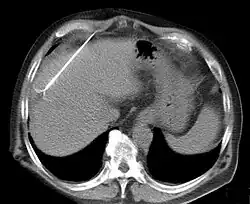

Computertomographie: Kontrolle der Lage der RFA-Nadel in einem Leberherd.

Die am Markt verfügbaren Geräte haben je nach Hersteller unterschiedliche Bauart mit dem Ziel, eine möglichst große und dabei kontrollierte Nekrosezone zu erzeugen. RITA/Angiodynamics verwendet dünne Aufspreizelektroden und einen 460 kHz-Generator, der 250 Watt leistet.[2] Radionics verwendet stabförmige, gekühlte Elektroden und gepulste 480-kHz-Wellen, bei max. 200 Watt Leistung. Vor- und Nachteile der Systeme halten sich bisher die Waage. Pro Elektrodenposition können ca. 2,4-2,8 cm große Gewebeareale zerstört werden. Dabei fließt ca. 1 Ampere Strom. Nach 12 bis 20 Minuten verkohlt das unmittelbar an der Elektrode gelegene Gewebe unter Gasbildung; damit steigen elektrischer Widerstand und Impedanz an, und die Energieübertragung kommt zum Erliegen. Zur Lagekontrolle der Sonden dient Sonografie oder Computertomographie.[3]